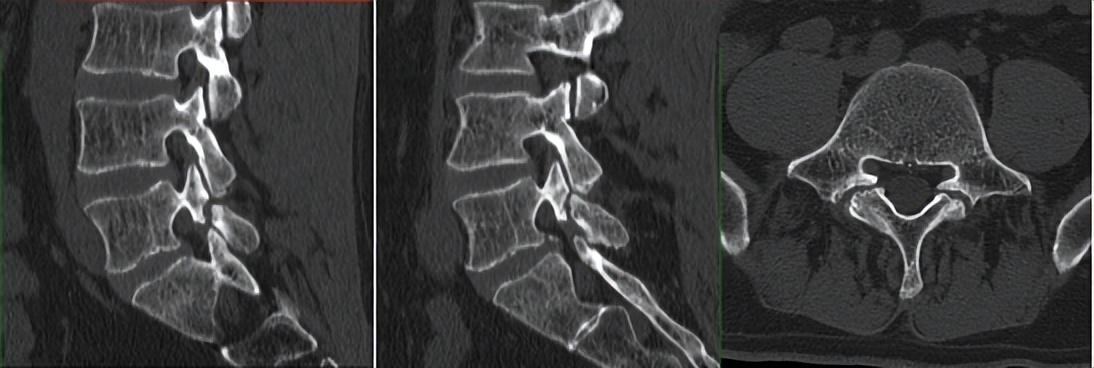

第一例病例为一名中年男性,腰4/5椎间盘突脱出并向下游离接近腰5/骶1椎间隙,为其实施VBE内镜下突出髓核单纯摘除术。患者术前腰痛伴右下肢疼痛麻木1个月余,右拇指背伸肌力明显下降。术后疼痛完全缓解,肌力较前部分恢复,有轻度麻木。

术前CT